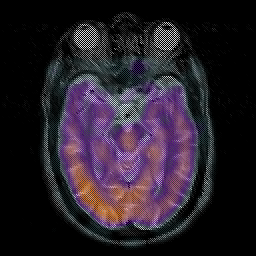

Subacute Stroke overlay -- Slice #9

[Home][Help][Clinical] Slice 9